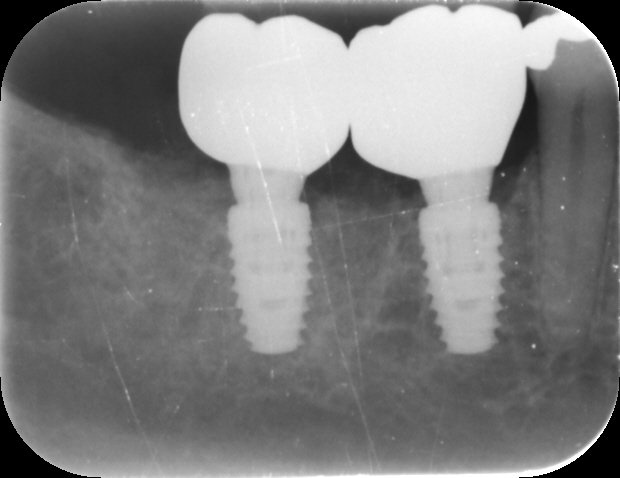

The implant crowns were constructed using custom-milled titanium abutments with a zirconia crown. Care was taken to ensure that any zirconia in contact with the tissues was polished rather than glazed to promote optimal soft tissue health. As seen in the post-treatment photos and x-rays, the hard and soft tissues have been well maintained, with excellent soft tissue thickness and a stable band of keratinised tissue achieved.

The immediate placement of the CONELOG® Progressive-Line implants in both molar sockets proceeded smoothly, achieving excellent primary stability. This approach not only preserved the existing bone and soft tissue but also provided a solid foundation for future prosthetic restoration. The use of MinerOss® Putty (allograft) played a crucial role in maintaining bone volume and soft tissue integrity, further contributing to the long-term success of the implants.